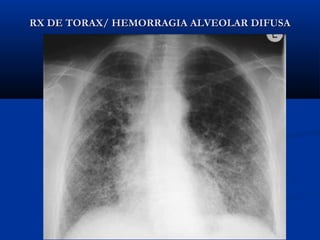

RX DE TORAX/ HEMORRAGIA ALVEOLAR DIFUSARX DE TORAX/ HEMORRAGIA ALVEOLAR DIFUSA

El paciente presentaba múltiples infiltrados bilaterales cavitados.